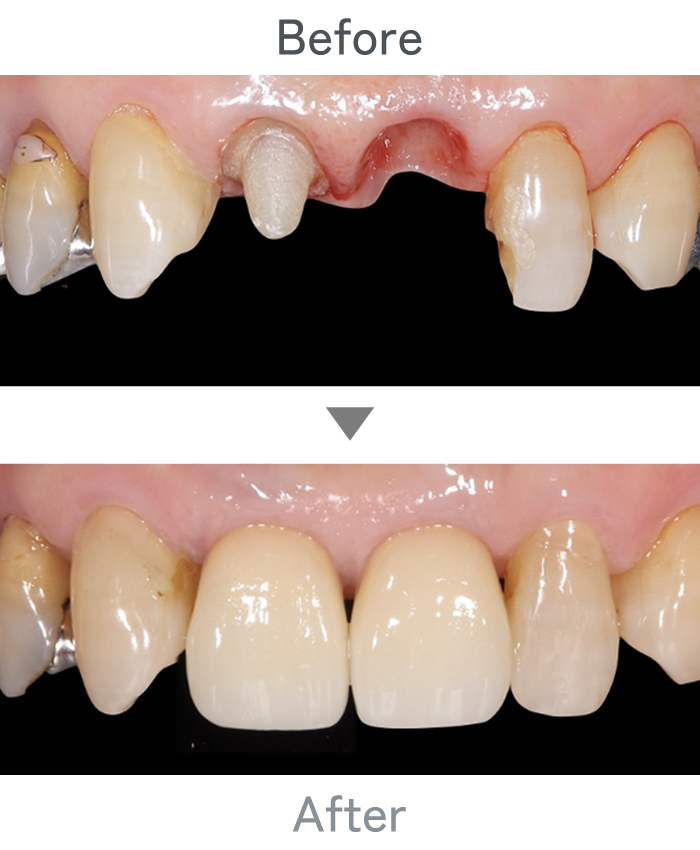

前歯のインプラント

主訴 前歯折れた

治療法 左上1番:インプラント治療

右上1番:セラミック治療

治療期間 4ヶ月半

費用 ・インプラント左上1番:300,000円

・インプラント左上1番上部構造:120,000円

・セラミック治療右上1番:120,000円

小 計:540,000円

消費税:54,000円

合 計:594,000円

※インプラント体、上部構造ともに『10年保証』

副作用

• メンテナンスが必要